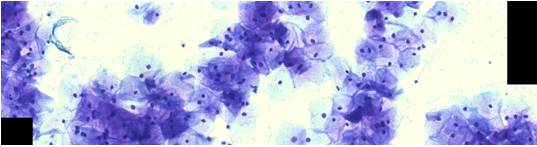

Микроскопия как метод исследования постоянно развивается в зависимости от технических достижений в области точной механики и оптики <#"588174.files/image001.jpg">